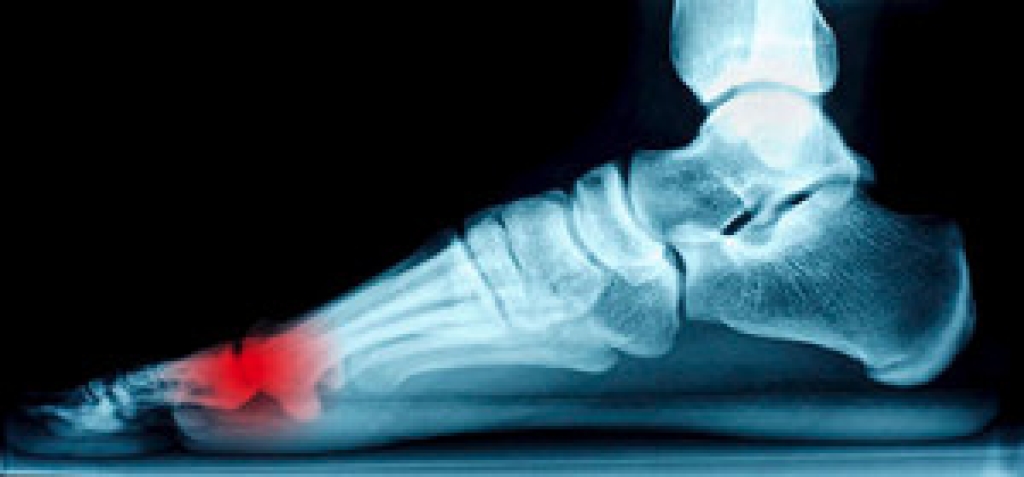

One problem that can occur is overpronation, which occurs when the arch of the foot flattens and tends to roll inward. This can cause pain and discomfort in your heels while you’re walking or even just standing up, trying to support your baby.